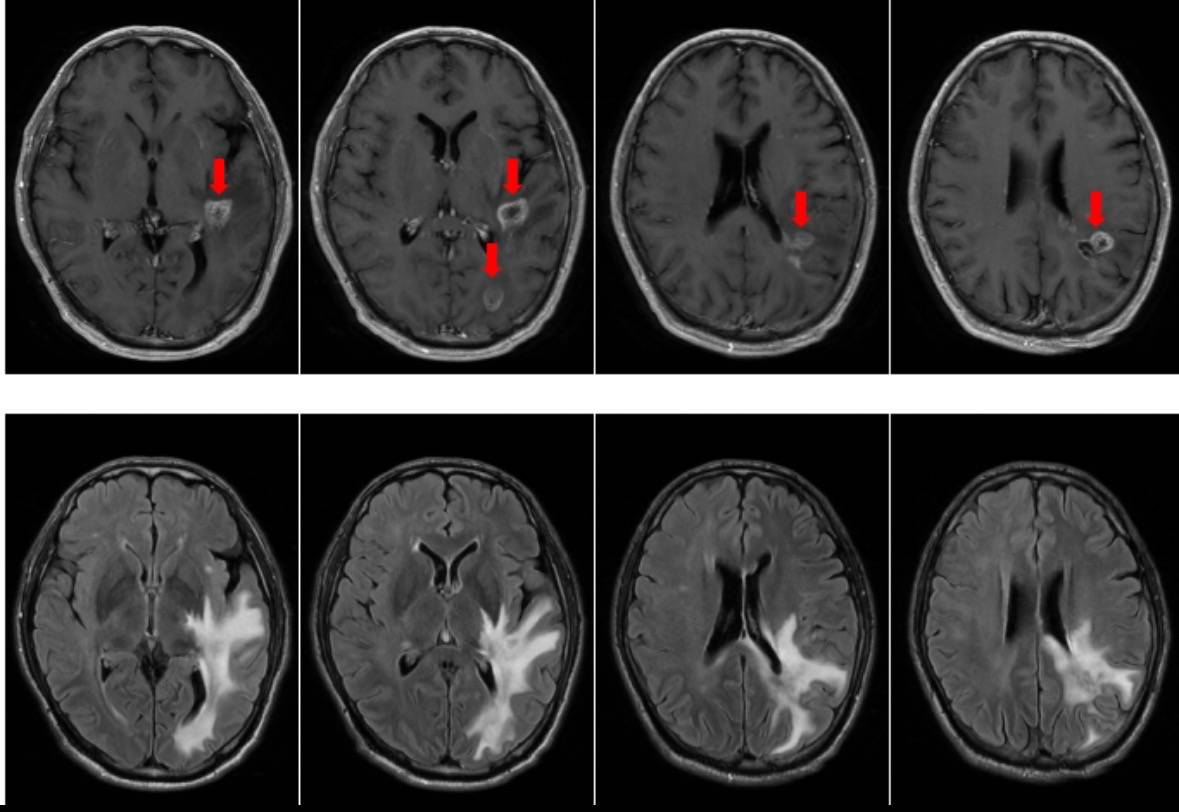

患者男性,54岁。2025年2月体检时发现左顶叶异常信号影,考虑胶质瘤可能性大。2025年3月8日行手术全切肿瘤,术后病理:(左顶)高级别胶质瘤,镜下呈胶质母细胞瘤形态,WHO 4级;建议行分子病理检测进一步明确诊断。免疫组化提示:MSH2、MSH6核表达缺失,提示微卫星不稳定。基因检测提示:MSI-H。术后行同步放化疗及替莫唑胺2周期化疗后,复查头颅核磁示颅内多发异常信号影,肿瘤复发可能性大(核磁见图1),患者出现近期记忆力下降的症状。患者为求进一步治疗就诊我科。

图1:2025-08-18头核磁提示肿瘤复发。